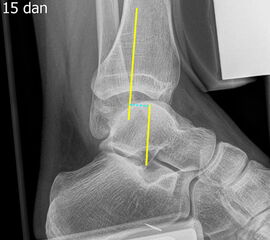

Sprunggelenk Mortise-Aufnahme mit Belastung

Positionierung:

• Der Patient steht, beide Beine sind geleichmäßig belastet.

• Der Fuß wird um ca. 20° innenrotiert. Der Zentralstrahl ist mittig auf den Gelenkspalt des oberen Sprunggelenks ausgerichtet.

• Die Röntgenkassette liegt dem Fuß dorsal an.

Kennzeichen des Röntgenbildes:

• Überlagerungsfreie Darstellung des Talus und der Malleolengabel.

• Der Gelenksspalt zwischen Talus und Fibula sowie zwischen Talus und Innenknöchel zeigt eine identische Breite.

• Der Weichteilmantel ist erkennbar.

Besondere Bemerkungen zum Beispielbild:

• Zustand nach Fremdkörperverletzung.

• Die röntgendichte Struktur (Metall) befindet sich im Bereich der lateralen Kalkaneuswand.

Zur Vollansicht und zum Lesen der Bildbeschreibung bitte die Bilder anklicken.